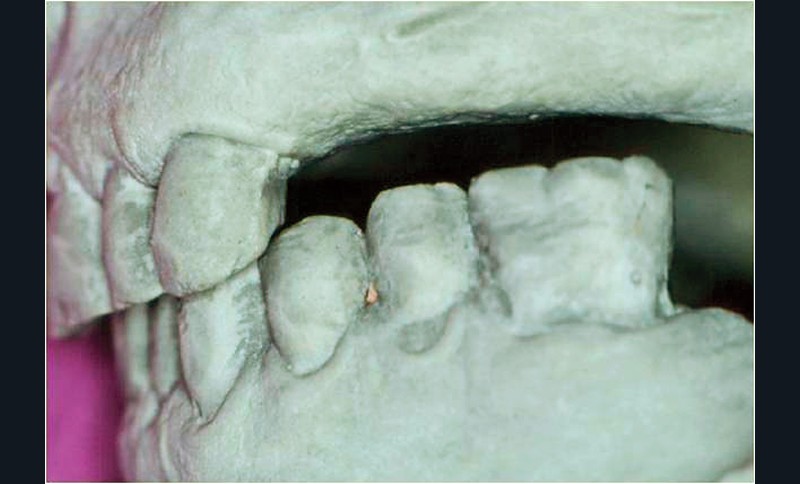

Sens vertical : la hauteur prothétique utilisable (HPU) correspond à la distance séparant le sommet de la crête des dents antagonistes ou du plan occlusal. Dans l’idéal, au niveau antérieur, cette hauteur est d’environ 4 mm et au niveau postérieur d’environ 7 mm (fig. 1).

Sa réduction se révèle être, souvent, un obstacle majeur à la réalisation d’une reconstitution prothétique satisfaisant…